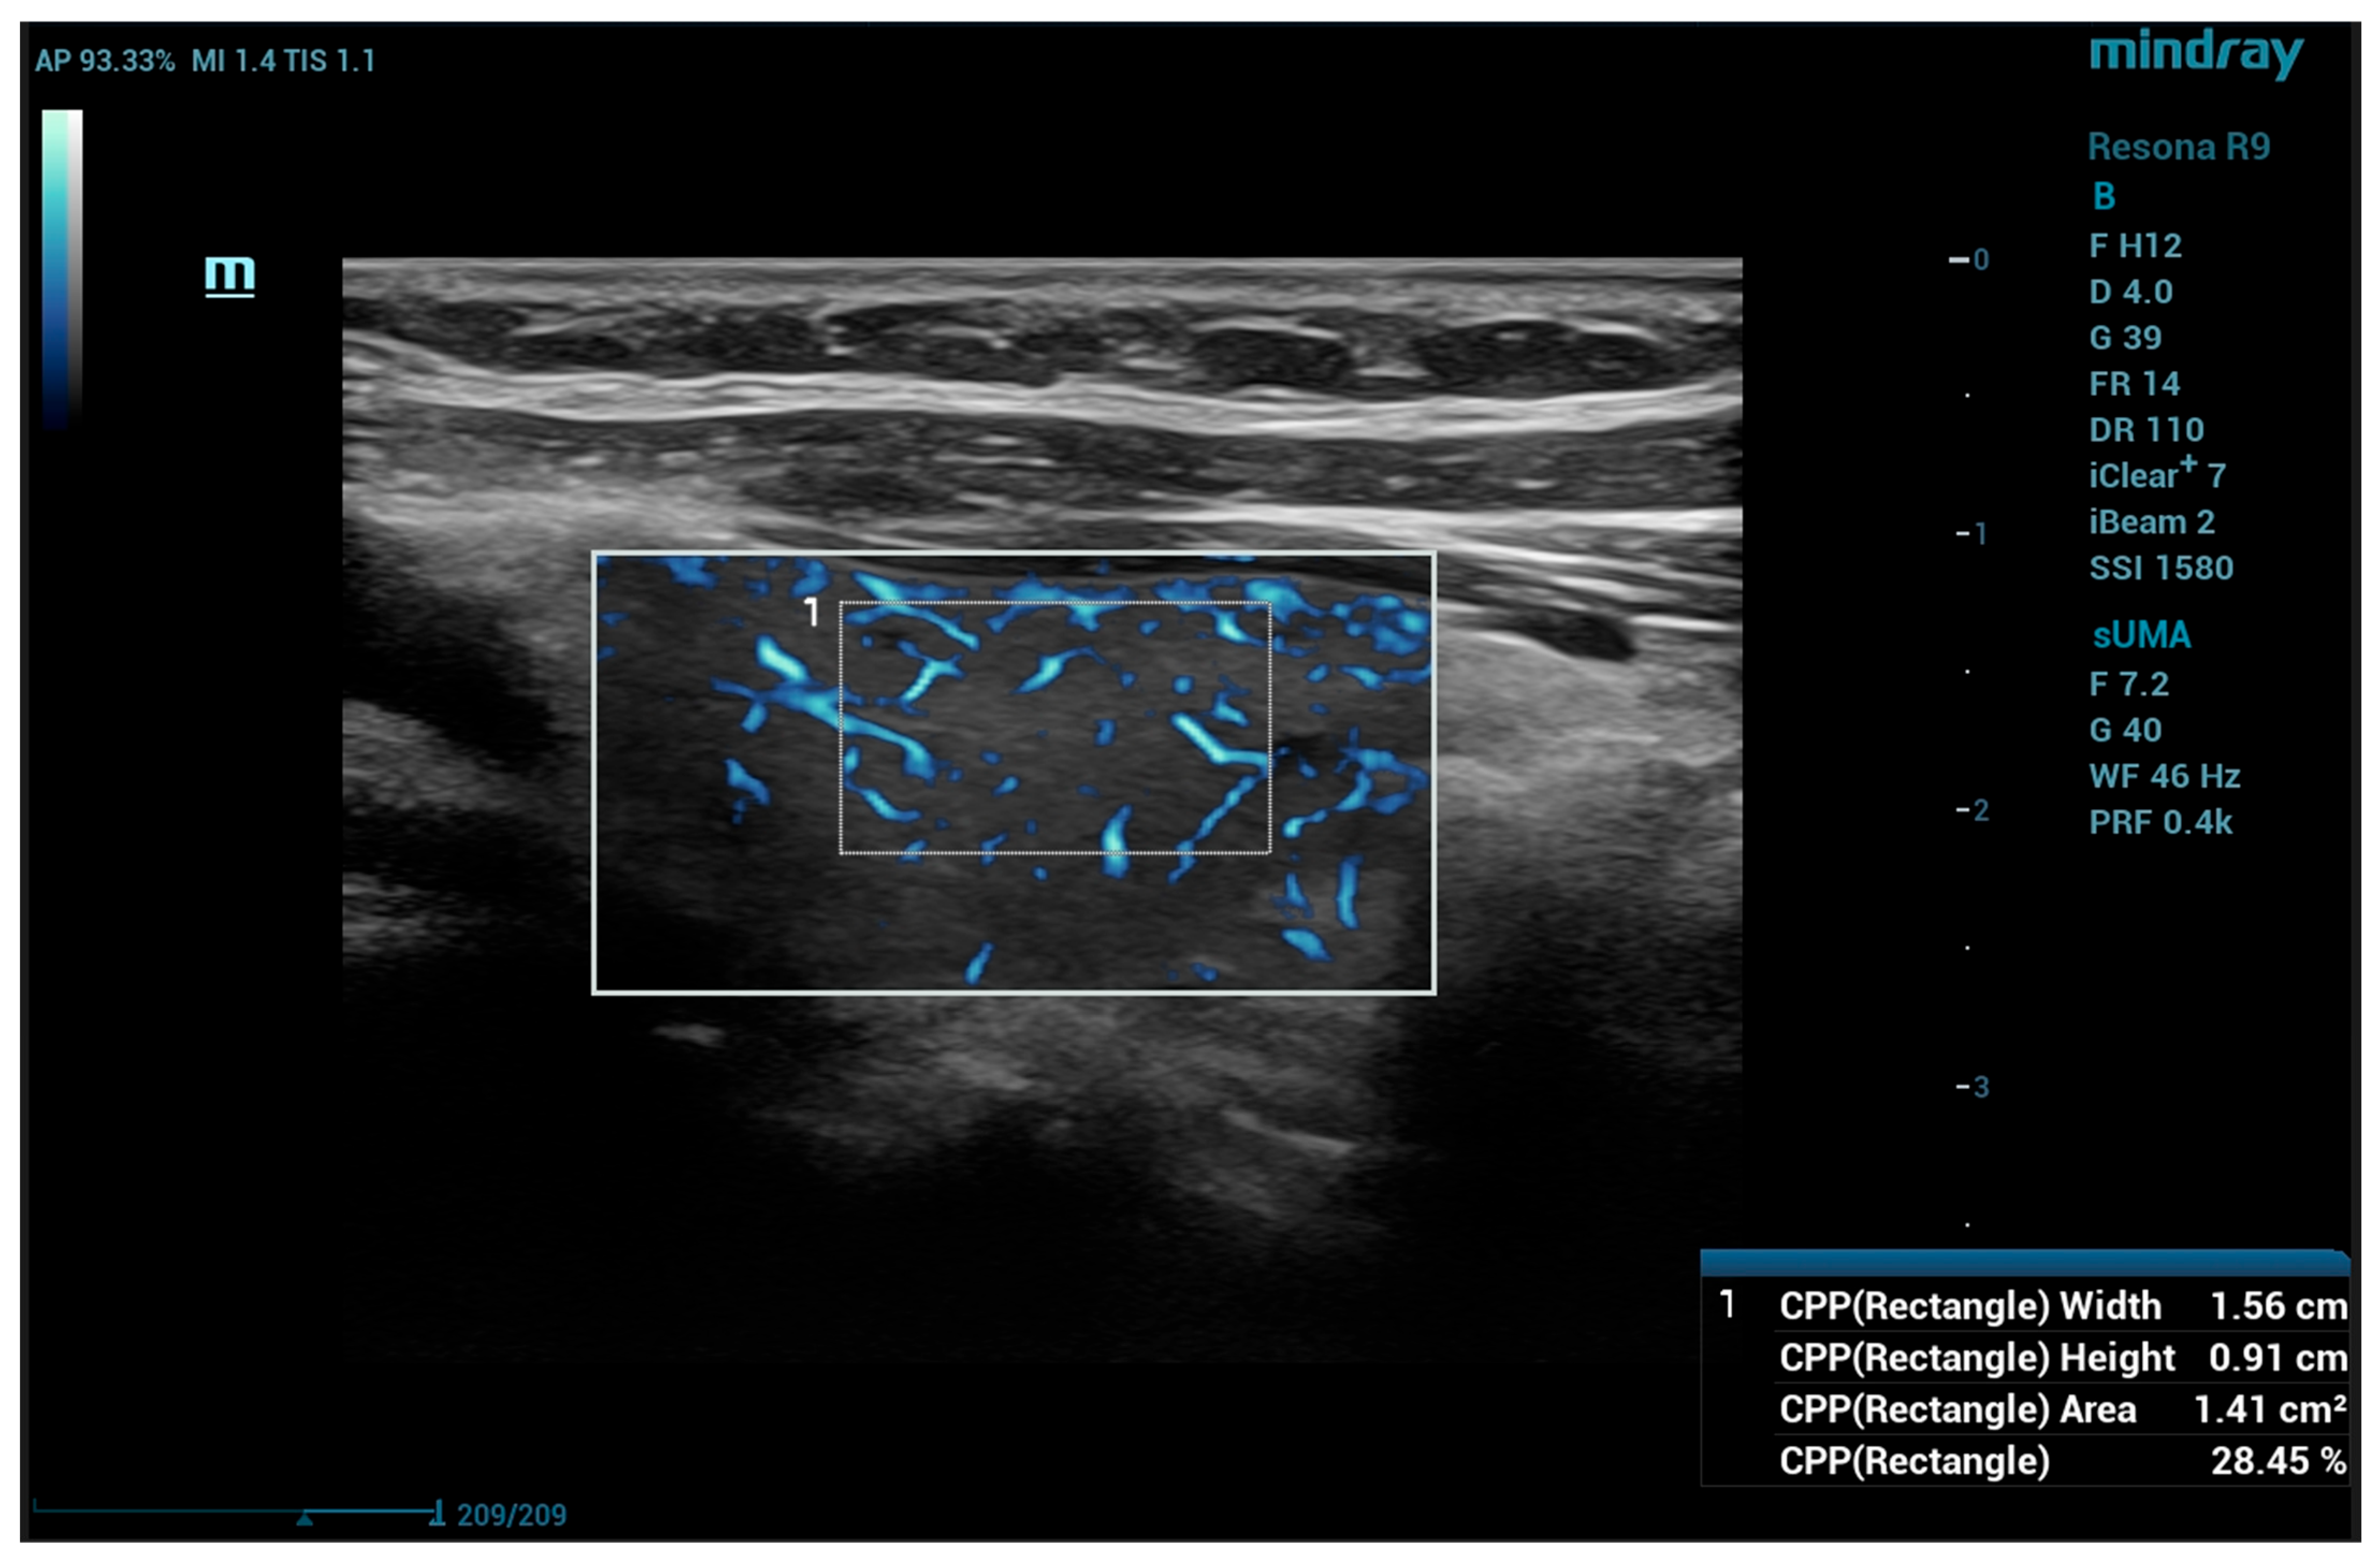

The same probe was used for sUMA measurement. In longitudinal view in B-mode, the area with the thickest portion of each lobe was selected and UMA (subset sUMA) was activated. The region of interest (ROI) box size was selected so to ensure the covering of most of the lobe height, starting superficial to the anterior thyroid capsule, with a lateral size of the ROI of a maximum 75% of the field of view. The gain was set to 40 in all cases; the wall filter frequency could be adjusted so order to reduce visible motion artifacts. Before acquiring the images for quantitative measurements, the patient was asked to hold still, with the probe also held still for 5–10 s in order to reduce artifacts caused by motion; if artifacts persisted, the patient was asked to hold their breath until stable images were obtained. The quantitative measurements were performed using the color pixel percentage (CPP) and the rectangle CPP measurement, covering a 0.8–1 per 1.5–2 cm box inside the lobe, adjusted to individual anatomical variants, avoiding areas with visible artifacts. The depth and CPP were registered for three measurements in each lobe (Figure 2). The median value of the three measurements was calculated in each case and the IQR.

Figure 2. Thyroid microvascularity using UMA technology: quantitative CPP measurement, in a patient without thyroid pathology; CPP—color pixel percentage; UMA—Ultra-Micro Angiography.